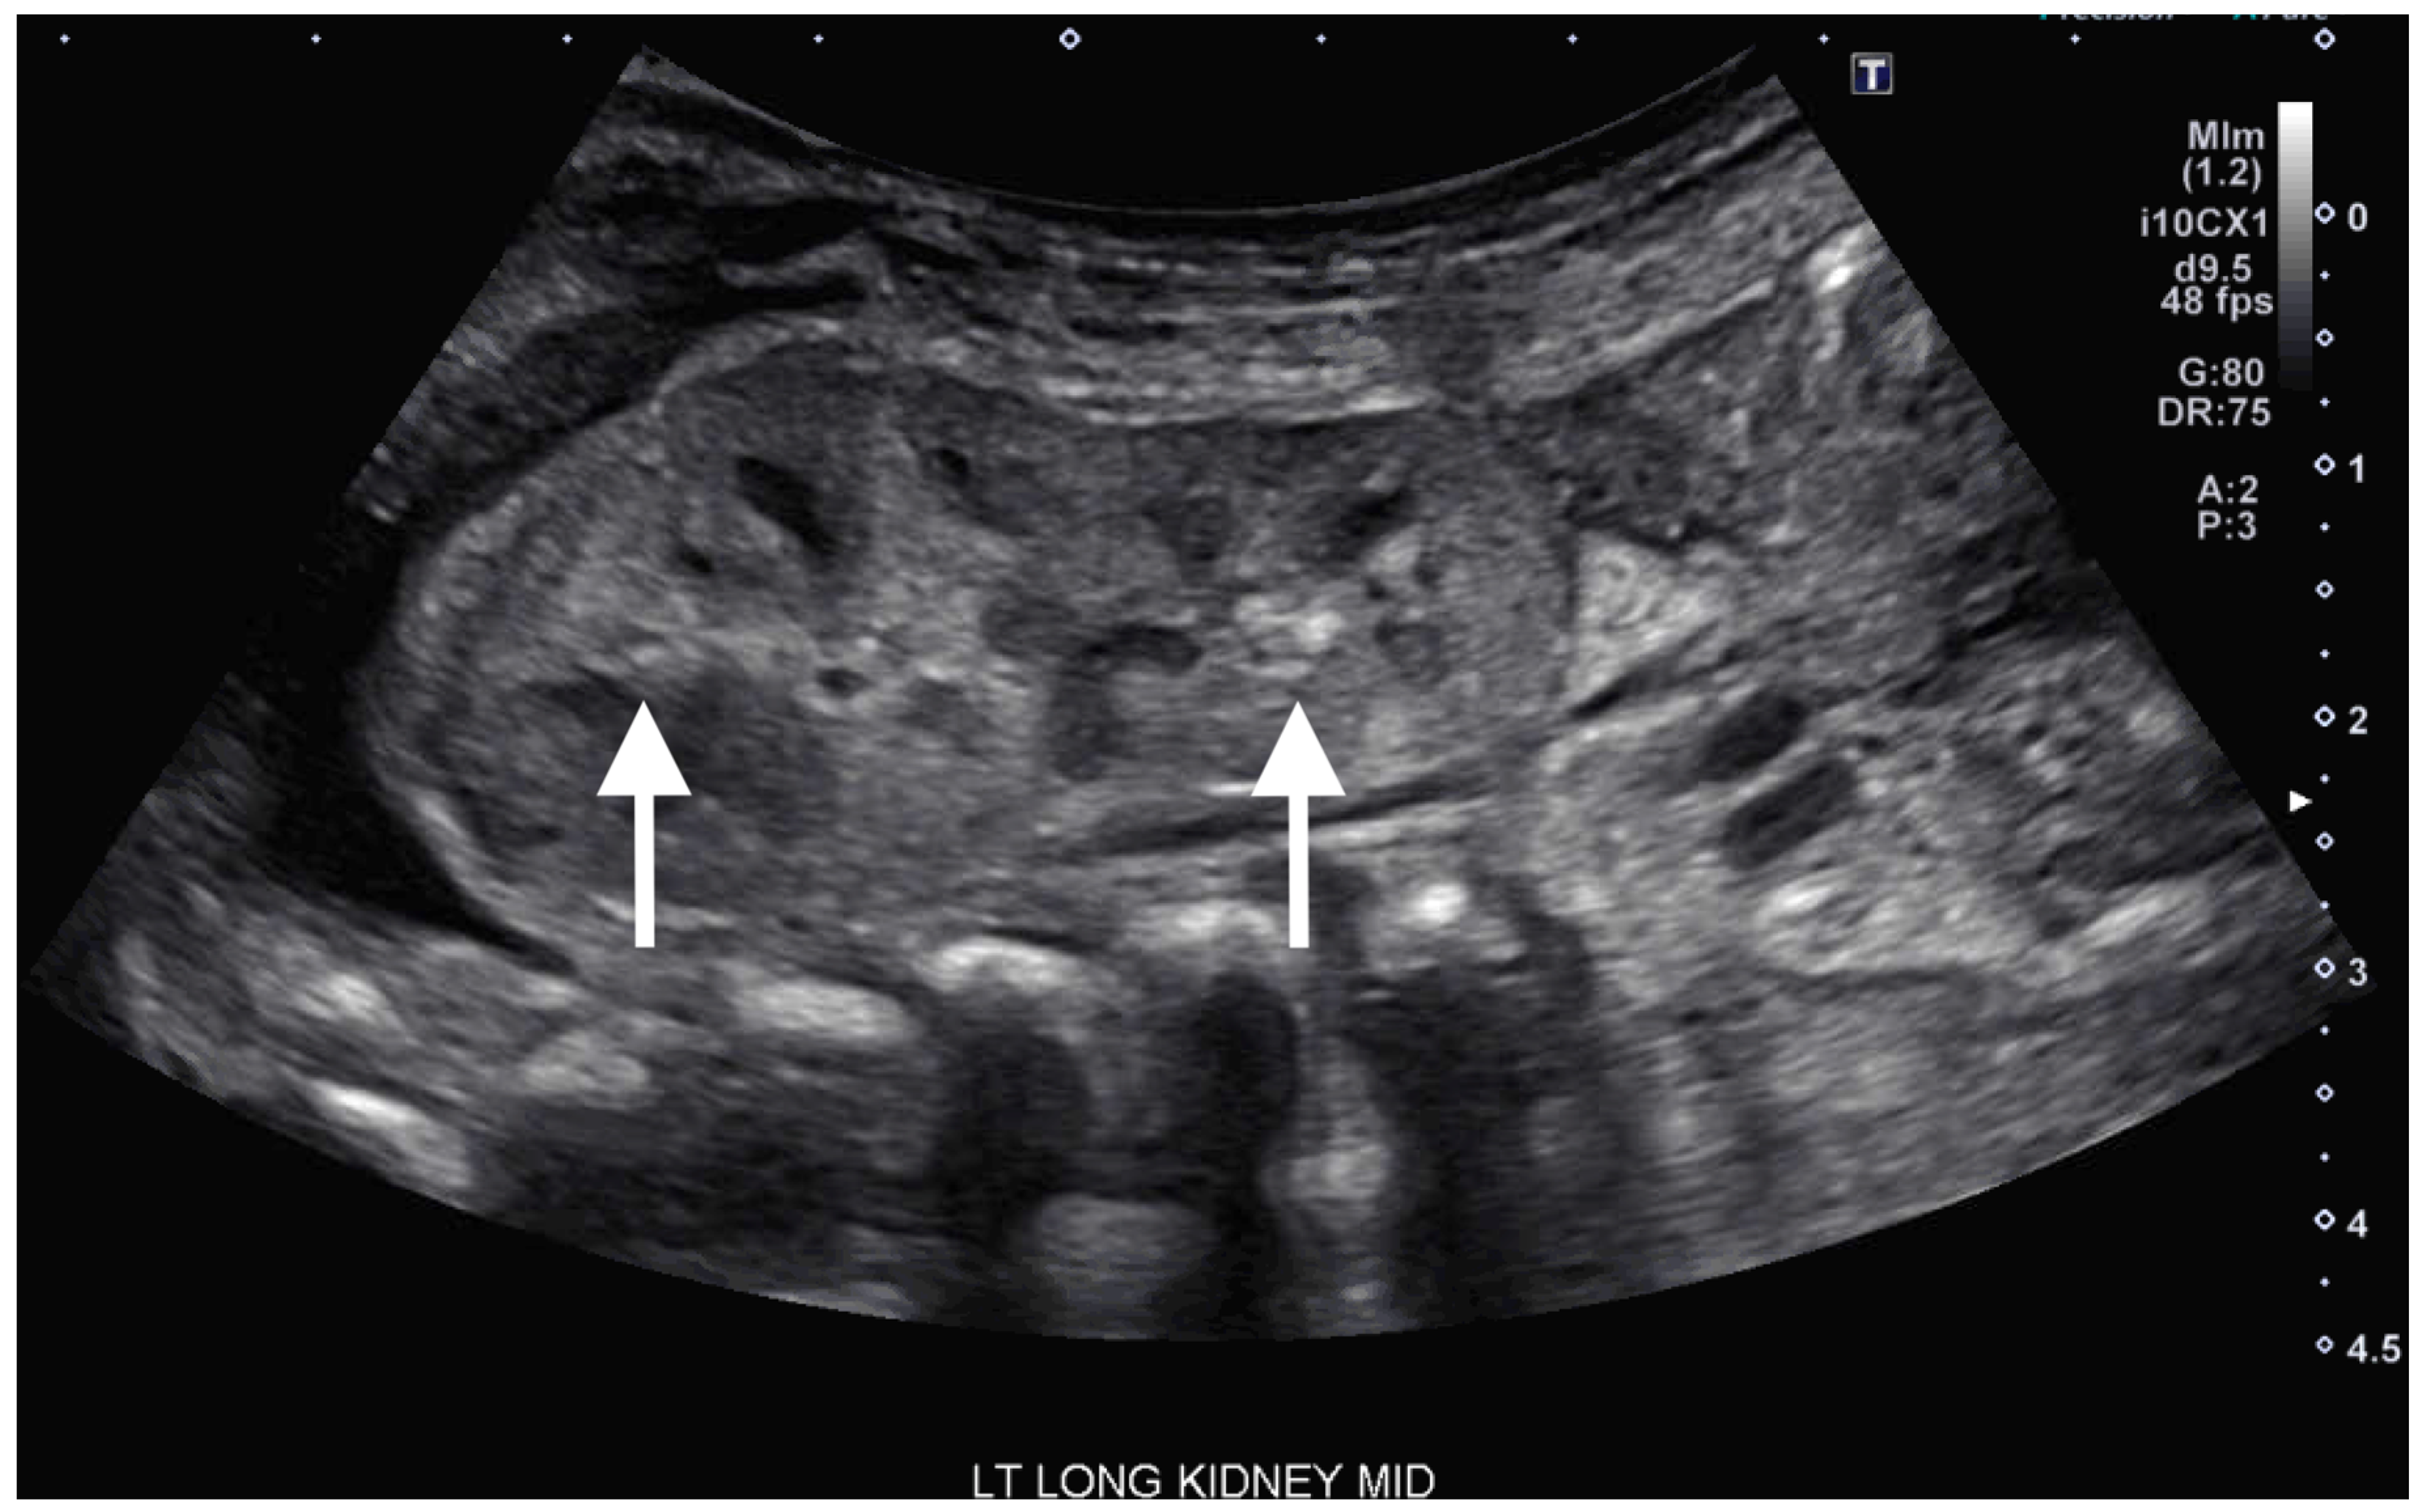

On DOL 5, the patient developed worsening abdominal distention with increased free fluid, rising lactate level, and continued oliguria with minimal brown-colored output, indicating potential bladder rupture. Renal ultrasound at that time demonstrated structurally normal kidneys and ureters, with contusive injuries in the parenchyma (Figure 1 and Figure 2). Pediatric urology was consulted. Diagnostic paracenteses and non-voiding cystogram showed no urinary leak. Computed tomography (CT) of the abdomen and pelvis was performed to further evaluate for free fluid or perforated viscus showed no renal contusion, but noted both kidneys had patchy opacification in the capsule and medulla, consistent with bilateral renal cortical necrosis (Figure 3). Cranial ultrasound was also performed at this time and showed focal parenchymal hemorrhage in the posterior portion of the left frontal lobe (Figure 4).

Figure 2.

Ultrasound of left kidney on day of life 5 showing increased focal echogenicity of the upper and lower poles (arrows).